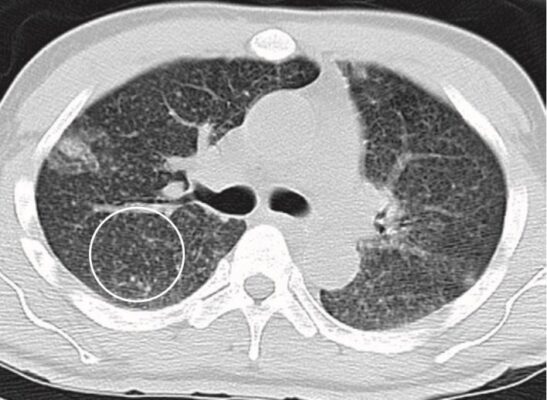

- Chụp CT có thể cho thấy nốt phổi đông cứng hoặc không đều có thể không rõ ràng trên phim chụp X quang thông thường (Hình 13).